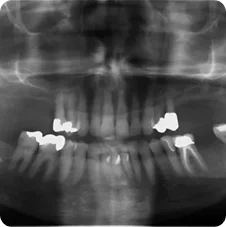

Case #1 was done with the coordination of Dr. Brian Assael D.D.S. Berkeley, CA. www.berkeleydds.com

Pre-operative

Case #2 done with the coordination of Dr. Brian Assael D.D.S. Berkeley CA. www.berkeleydds.com